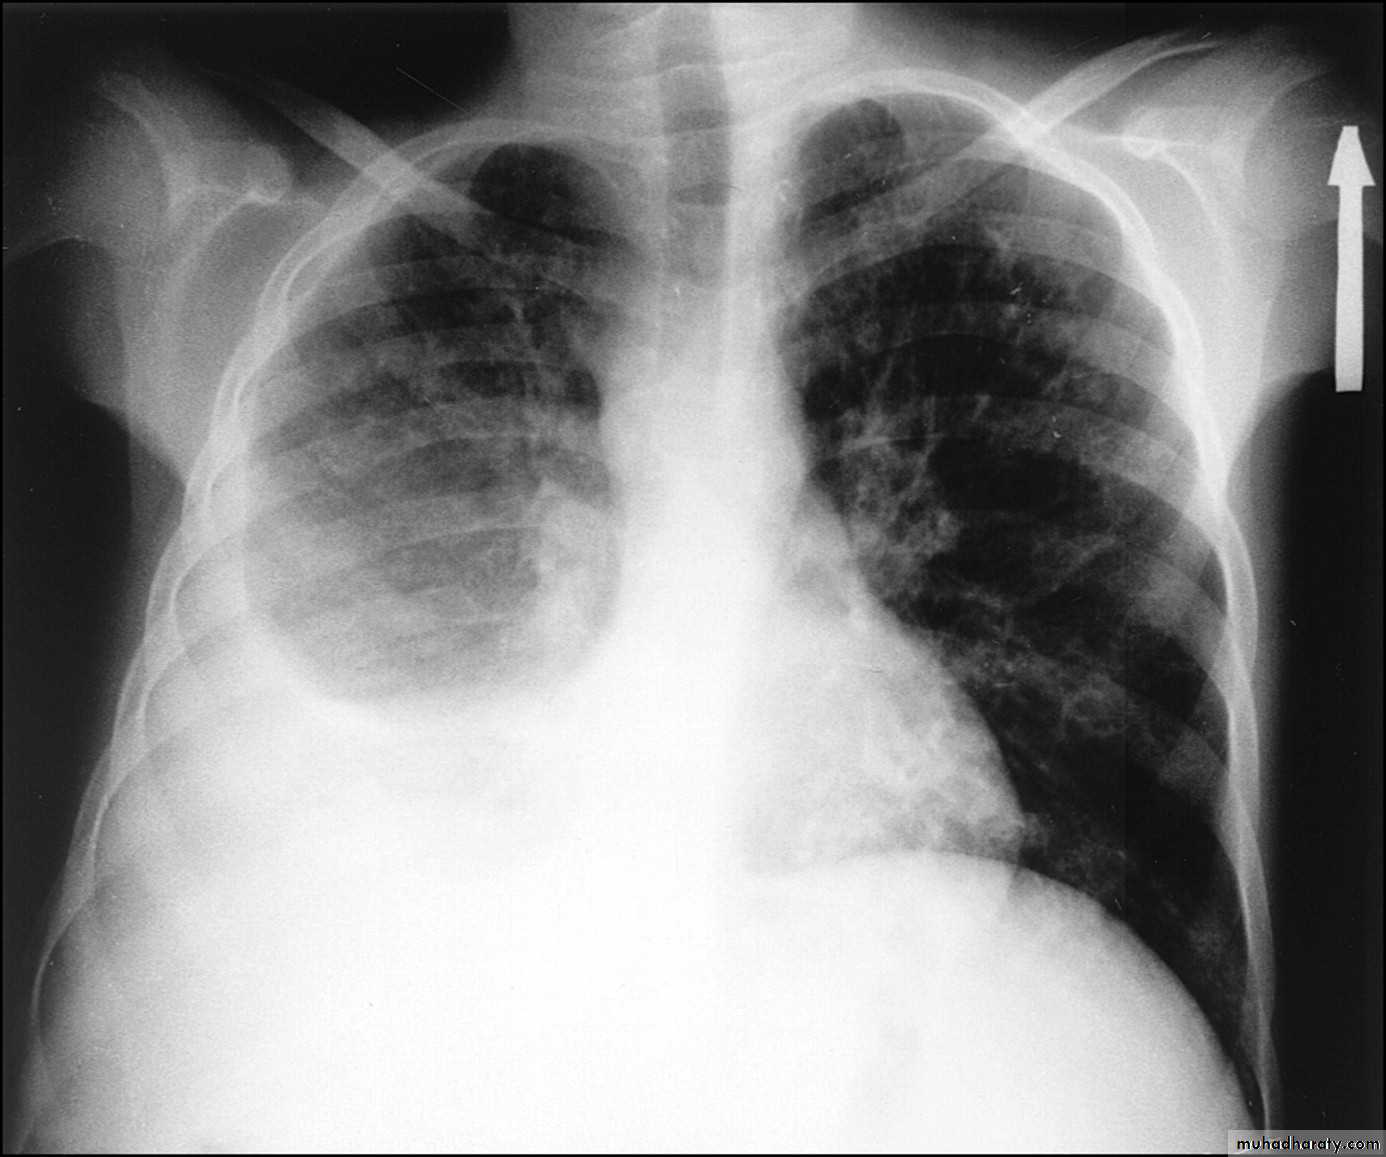

Chest radiograph

A pneumothorax is, when looked for, usually relatively easily appreciated. Typically they demonstrate:

visible visceral pleural edge see as a very thin, sharp white line

no lung markings are seen peripheral to this line

the peripheral space is radiolucent compared to adjacent lung

the lung may completely collapse

the mediastinum should not shift away from the pneumothorax unless a tension pneumothorax is present

A tension pneumothorax

A tension pneumothorax occurs when intrapleural air accumulates progressively in such a way as to exert positive pressure on mediastinal and intrathoracic structures. It is a life threatening occurrence requiring rapid recognition and treatment is required if cardiorespiratory arrest is to be avoided.Radiographic features

A pneumothorax will have the same features as a run-of-the-mill pneumothorax with a number of additional features, helpful in identifying tension. These additional signs indicate over expansion of the hemithorax:

ipsilateral increased intercostal spaces

shift of the mediastinum to the contralateral side

depression of the hemidiaphragm

tension pneumothorax